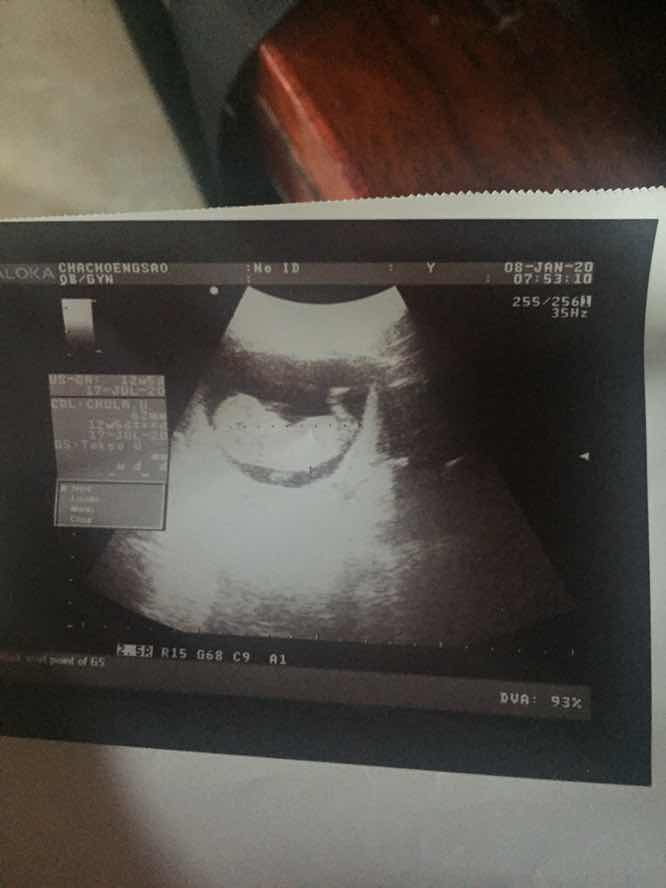

9w6d ค่ะ

Post reply image